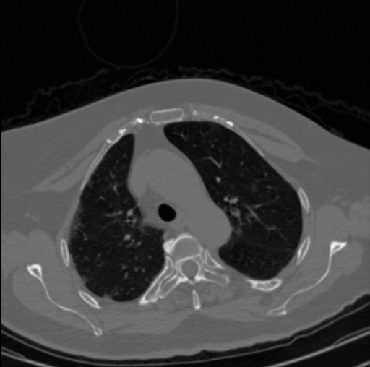

Early and reliable COVID-19 diagnosis based on chest 3-D CT scans can assist medical specialists in vital circumstances. Deep learning methodologies constitute a main approach for chest CT scan analysis and disease prediction. However, large annotated databases are necessary for developing deep learning models that are able to provide COVID-19 diagnosis across various medical environments in different countries. Due to privacy issues, publicly available COVID-19 CT datasets are highly difficult to obtain, which hinders the research and development of AI-enabled diagnosis methods of COVID-19 based on CT scans. In this paper we present the COV19-CT-DB database which is annotated for COVID-19, consisting of about 5,000 3-D CT scans, We have split the database in training, validation and test datasets. The former two datasets can be used for training and validation of machine learning models, while the latter will be used for evaluation of the developed models. We also present a deep learning approach, based on a CNN-RNN network and report its performance on the COVID19-CT-DB database.